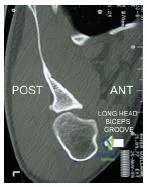

Which of the following conditions does this computerizd tomography scan (Slide) most likely represent:

Correct Answer: Osteoid osteoma

This is an osteoid osteoma of the fourth lumbar vertebra in a patient who experienced night pain and relieved the pain with nonsteroidal anti- inflammatory drugs. The location of a sclerotic nidus in the posterior elements of the vertebrae is typical for this disorder. Excision of the osteoid osteoma resulted in prompt pain relief for this patient.